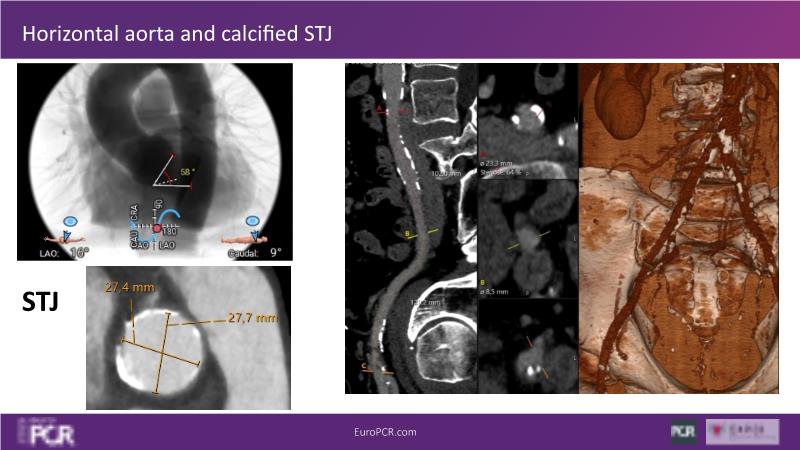

Watch this session to discover insights into patient-prosthesis mismatch and strategies to mitigate risks, delve into the significance of aortic valve commissure for coronary alignment optimization during TAVI, and explore solutions for common TAVI challenges such as peripheral vessel tortuosity and asymmetric valve calcifications in large or small aortic annuli.

- To discuss options to overcome common daily challenges of TAVI: peripheral vessel tortuosity, horizontal aorta, asymmetric valve calcifications in large, or in small aortic annuli